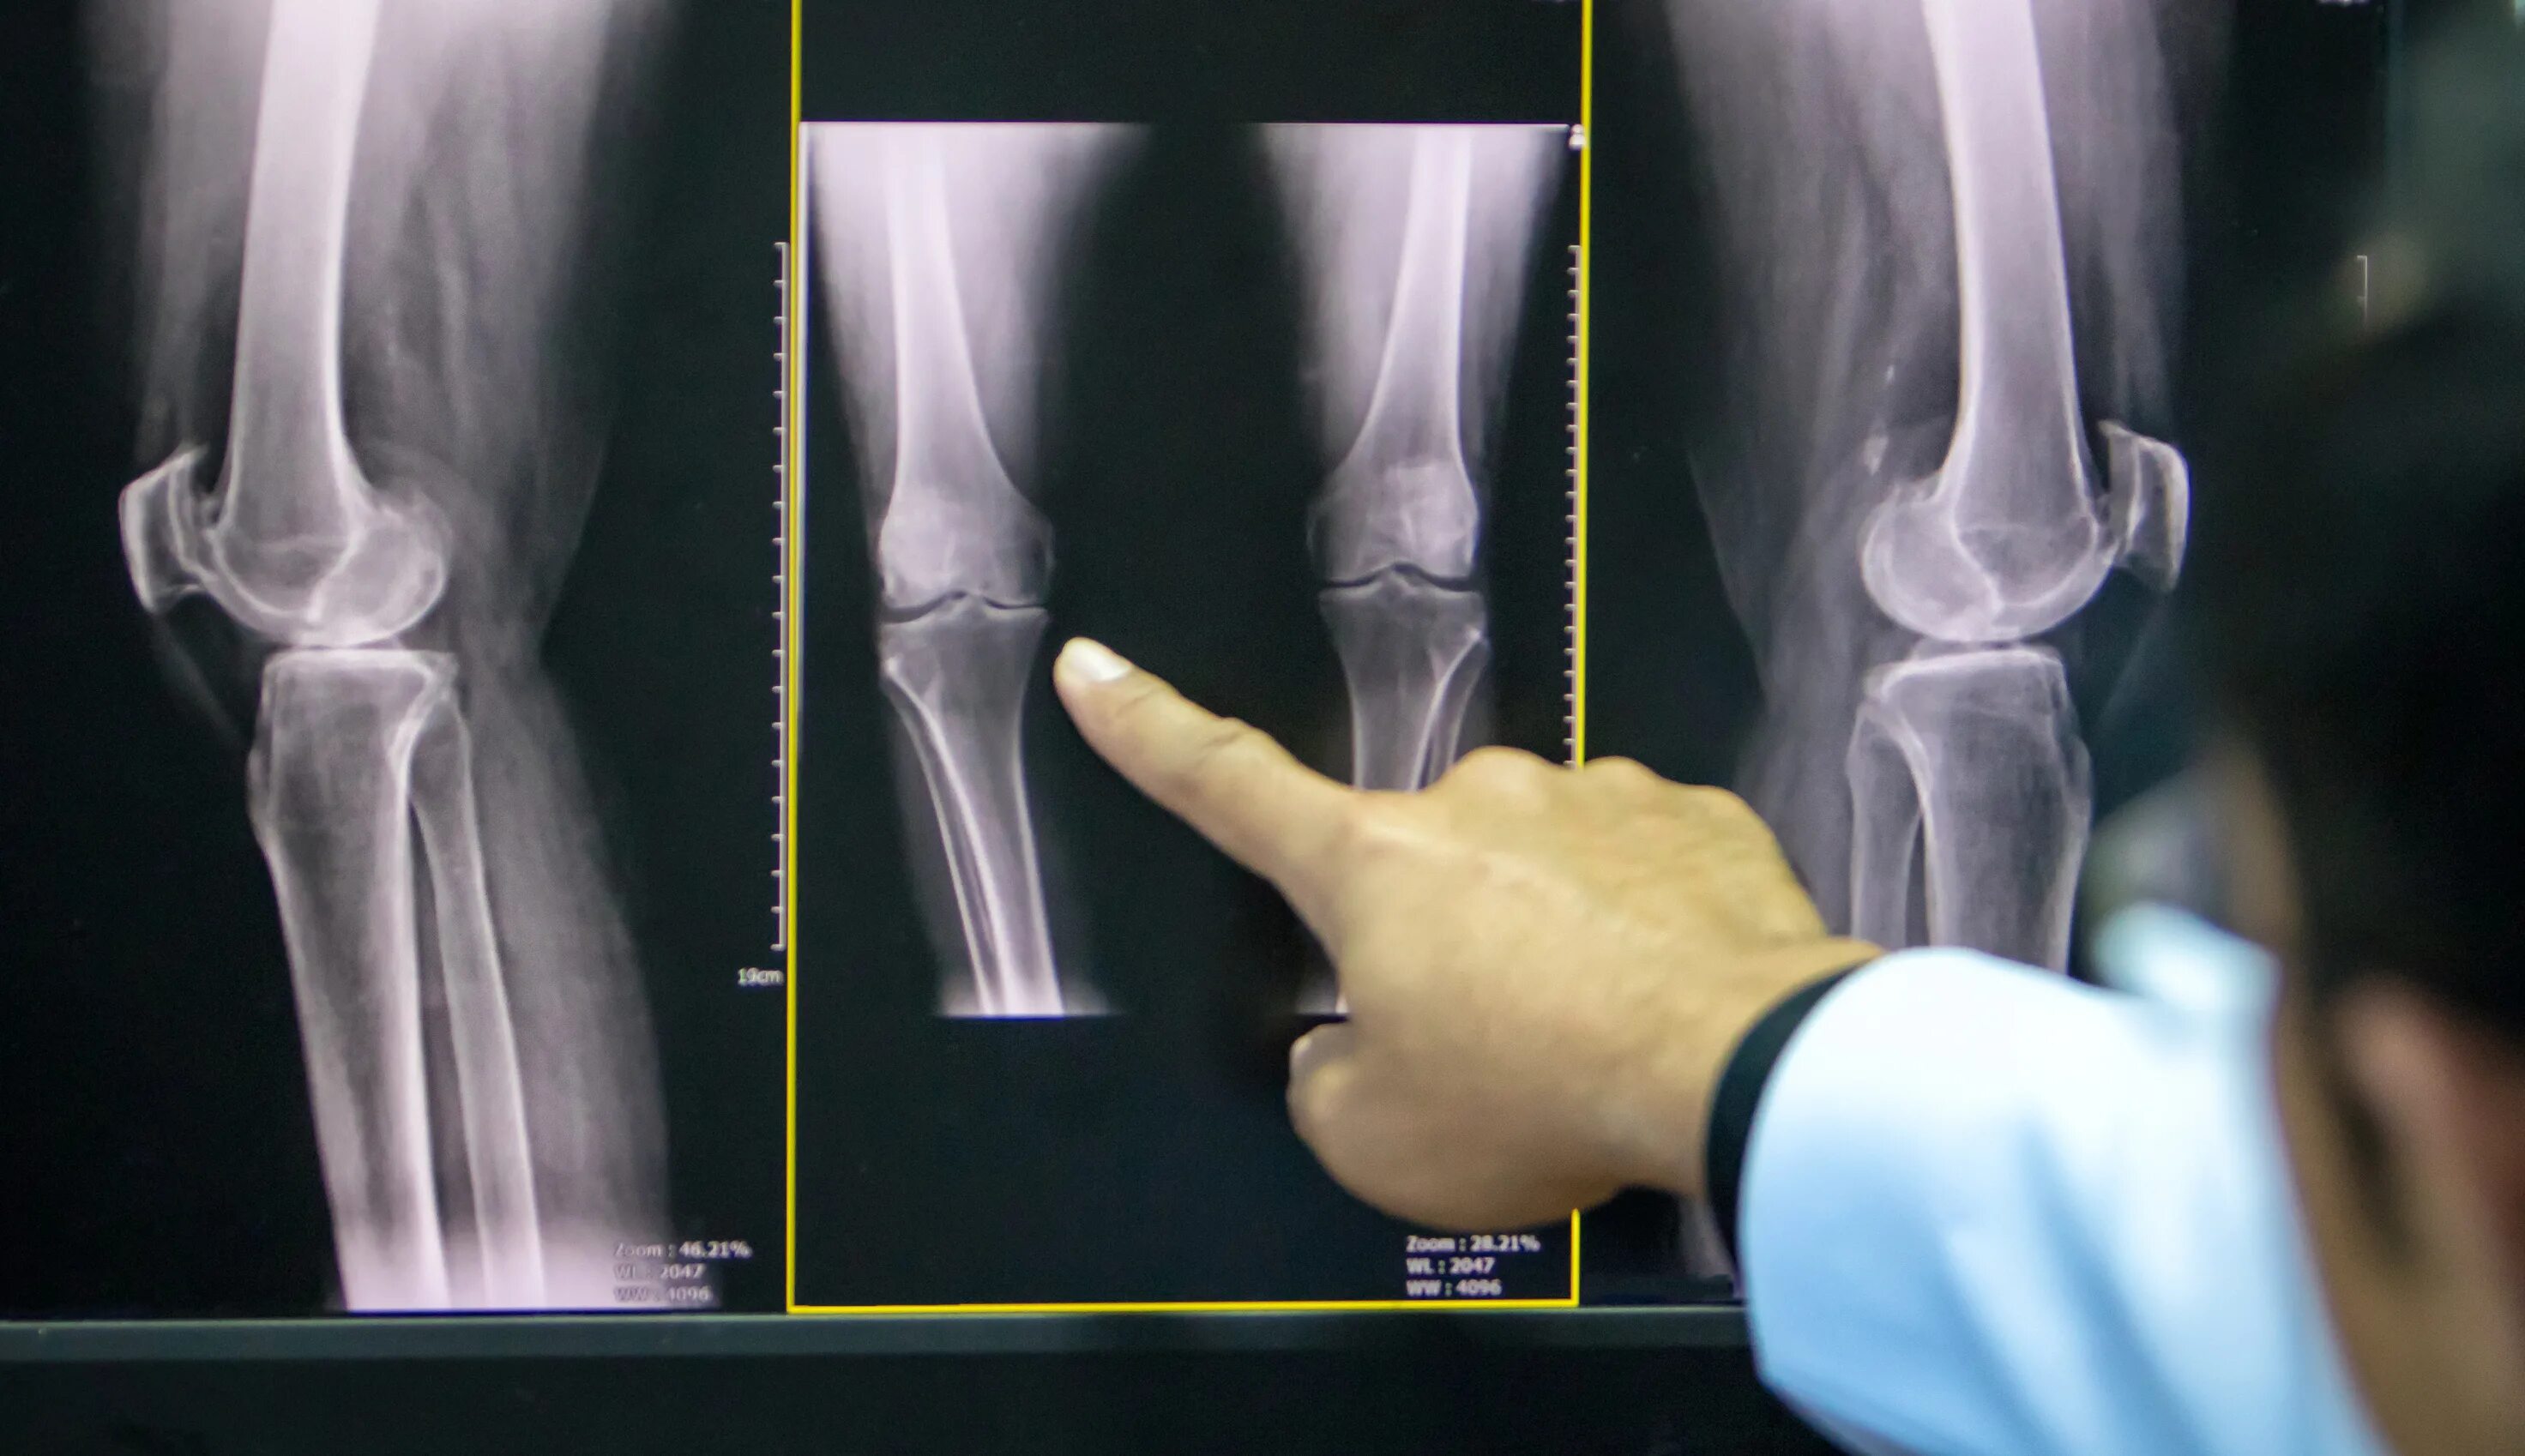

Дисторсия коленного